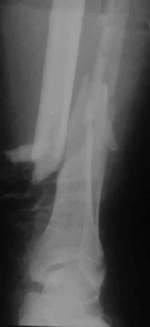

| Die offene Unterschenkelfraktur wird mit dem dynamischen Fixateur

Monotube versorgt. Durch die zusätzliche Fixierung mit Drähten

ist die Faktur nicht dynamisch stabilisiert. Trotz primärer Frakturheilung

und baldiger Belastung ist keine Knochenbildung zu erkennen. |